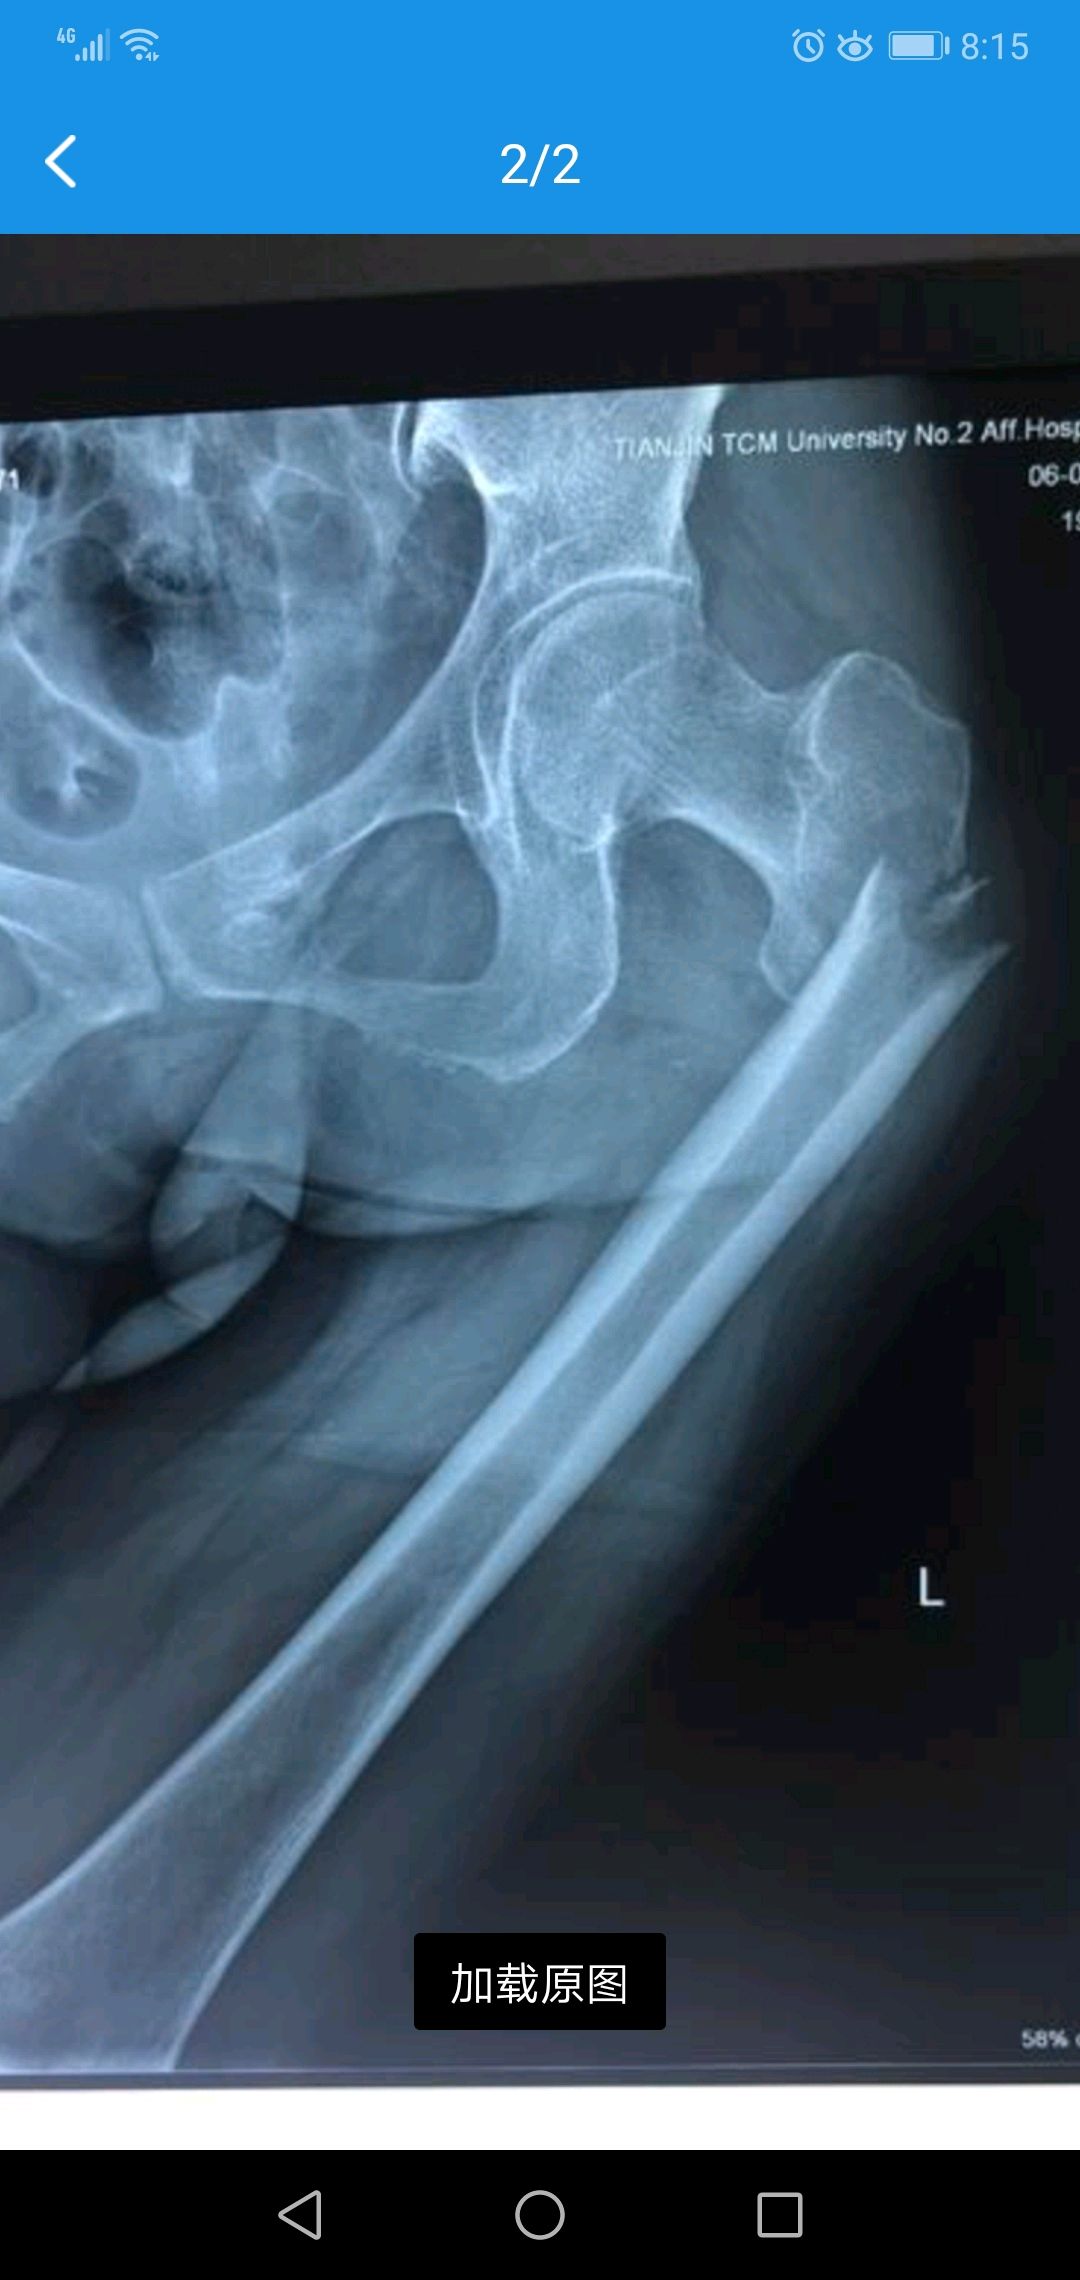

转子下骨折

图片尺寸2000x2667